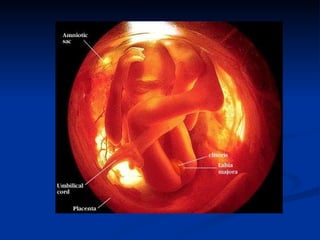

The document discusses embryonic development in humans. It begins with fertilization and cleavage, followed by gastrulation where the three germ layers are formed. During this time the primitive streak and Henson's node develop. Organogenesis then occurs, forming individual organs from the germ layers. Mammalian development includes the allantois and notochord. In humans, the placenta forms and gestation occurs over three trimesters, with major organ structures present by the first trimester.